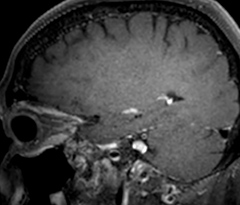

Fast MS protocol with optional sequences

The abbreviated MS protocol for brain is only around 9 minutes, so in case of suspected multiple sclerosis, one or two more advanced sequences may be added, such as PSIR (phase sensitive inversion recovery) or susceptibility-weighted sequences to help us make more confident diagnoses in these inflammatory cases.

In this example, the optional 3D multishot susceptibility weighted sequence with 0.6 mm isotropic voxels is 2 lesions with a central vein sign (arrows) and one lesion with a phase-rim sign (arrowhead). The total scan time, including SmartBrain and axial PD/T2 3mm, is 11:10 min. and is 18:30 min. with the optional 3D PSIR and 3D SWI multishot included.

“In multiple sclerosis patients, we increasingly include a multishot susceptibility sequence [3] in our routine cases, thanks to the shorter scan times. Our abbreviated MS protocol for brain is around 8 to 9 minutes, so we can ask for one or two additional sequences to visualize the central veins, or to get an additional contrast to better depict posterior fossa lesions. In cases of white matter lesions of unknown significance on FLAIR images, for example when we see high signal hyperintensities in the brain, we can add on more advanced sequences such as PSIR (phase sensitive inversion recovery) or susceptibility-weighted sequences to help us in distinguishing between MS and nonspecific or vascular abnormalities in these inflammatory cases.”